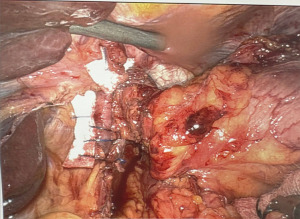

Posterior cruroplasty was performed in 34% of patients (n=38), while 66% (n=73) underwent combined anterior and posterior crural closure (Figure 2). In cases with attenuated crural fibers, the repair was reinforced with felt pledgets (Figure 3). Mesh reinforcement was required in only one patient due to a large diaphragmatic defect with loss of domain.